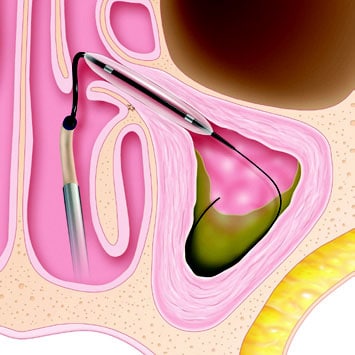

Chronic sinusitis and reoccurring sinus infections are unpleasant to deal with. If medications do not effectively relieve your symptoms, you may be a candidate for a procedure called Balloon Sinuplasty. During this minimally invasive surgery, a small balloon is placed inside of the nose to expand the sinus passages, which allows them to drain better. Recovery time is significantly shorter than with traditional sinus surgery, and the results are just as effective.

A Balloon Sinuplasty procedure can be performed in our office, often in under 30 minutes. Our ENT will give you a local anesthetic and an oral sedative to ensure that you are comfortable. Next, they’ll use an endoscope to guide the balloon catheter into your sinuses. The balloon is then inflated to expand the sinus opening.

Balloon sinuplasty involves little to no tissue removal inside the nose and sinuses. At the present time, it is used to open the frontal, maxillary and sphenoid sinuses. Because the technique was recently introduced, surgeons are still learning which patients it will work best for and when it is the appropriate choice of device for surgery. Situations that balloon sinuplasty is usually not appropriate for are cases of large nasal polyps or significant scarring from previous sinus surgery.

The technology uses small, soft, flexible devices that enter entirely through the nostrils. These devices gently open blocked sinus openings in many cases, without tissue or bone removal.